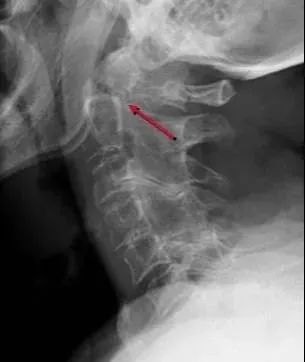

四、Hangman’s骨折

是C2最常见的骨折,也是最常见的颈椎骨折,多由过伸及压缩外力造成,骨折线经C2椎弓根,C2向前滑脱,不伴有神经损伤。